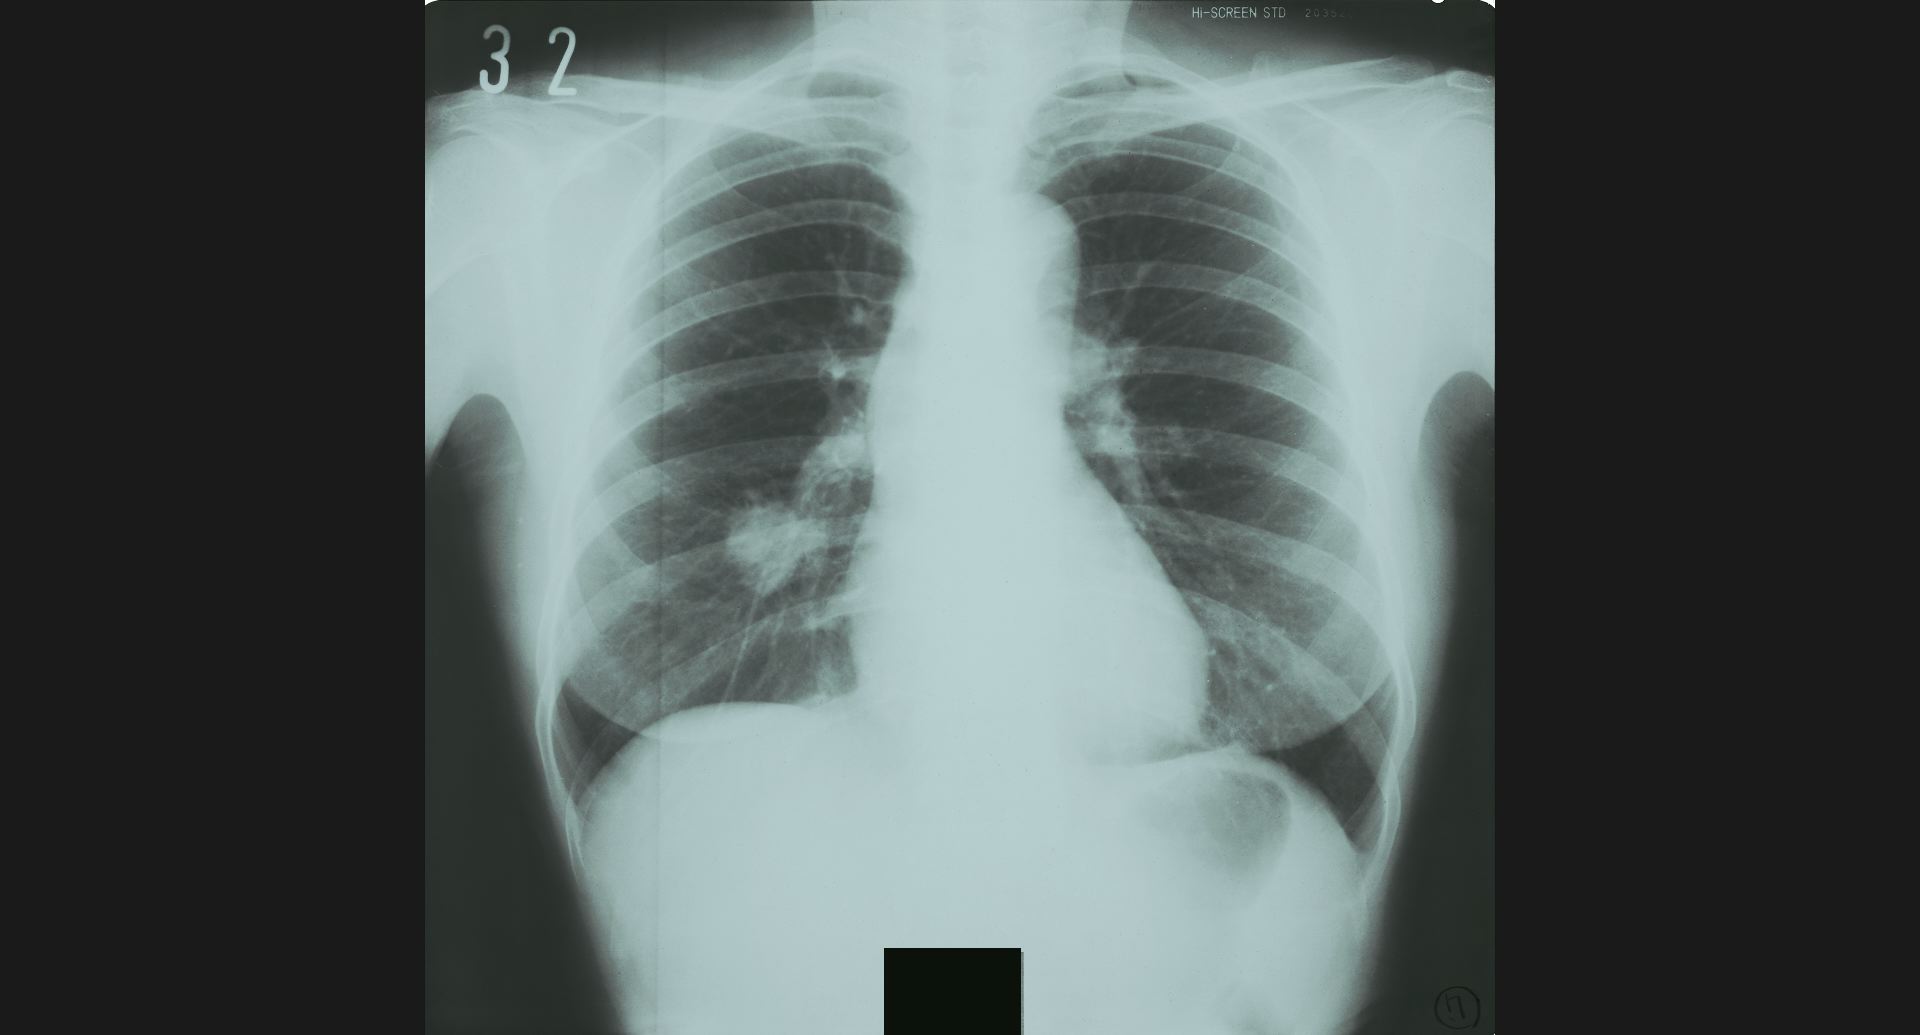

fig.9(94KB) :Pneumoconiosis

細かい斑状陰影。